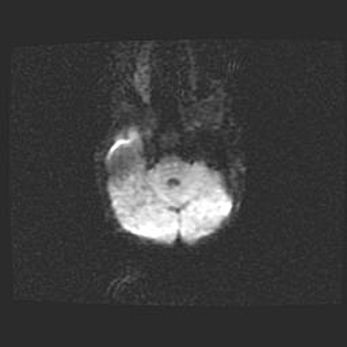

Подострая гематома правой гемисферы мозжечка.

Наружная гидроцефалия.

Возраст: 15 дней

Вес: 3100 г

Пол: женский

Окружность головы: 37 см

Срок гестации: 35-36 недель

При открытой наружной форме гидроцефалии у новорожденных расширяются и переполняются субарахноидные пространства.

Кровоизлияния в мозжечок имеют две клинико-анатомические формы: полушарные гематомы и кровоизлияния в червь.

К появлению этой патологии может привести: повреждения головного мозга, возникающие в результате асфиксии и гипоксии плода при беременности, или травмы во время родов. Редко гематома мозжечка может быть результатом первичной коагулопатии и сосудистой мальформации, диссеминированном внутрисосудистом свертывании, изоиммунной тромбоцитопении.